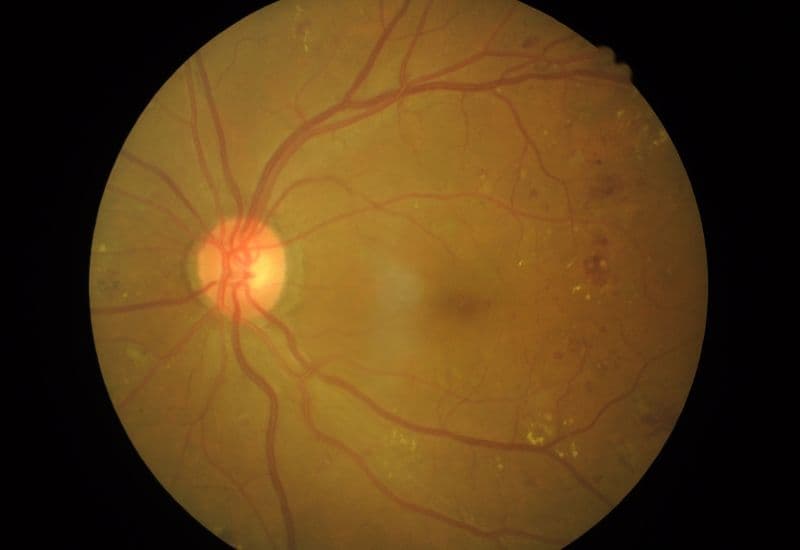

Tân mạch hắc võng mạc là hiện tượng các mạch máu mới, bất thường hình thành trên bề mặt hoặc bên trong võng mạc. Khác với các mạch máu bình thường, những mạch máu mới này thường mỏng, dễ vỡ, có thể gây ra các biến chứng nghiêm trọng như xuất huyết, phù nề võng mạc, thậm chí là bong võng mạc.

Những mạch máu mới trên bề mặt hoặc bên trong võng mạc thường mỏng, dễ vỡ.

– Kiểm tra đáy mắt: Bác sĩ sử dụng một thiết bị đặc biệt để quan sát trực tiếp võng mạc và các mạch máu. Tình trạng tân mạch hắc võng mạc có thể được xác định thông qua các mạch máu mỏng, uốn lượn bất thường trên bề mặt võng mạc.